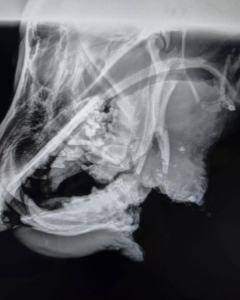

Diamond was a young male German Shepherd with a badly broken jaw that had been left untreated for too long. We knew from the moment we met him that he deserved every possible chance at a pain-free life. We rushed him to Guardian Veterinary Centre, where experts evaluated and treated him with compassion. Despite their best efforts, the extent of the damage meant there was no viable fix. We take comfort in knowing his last moments were spent with people who cared about him. Thank you to the Guardian Veterinary Centre team for their commitment, and to Amber who volunteered to pick Diamond up and make the long trek into the city.